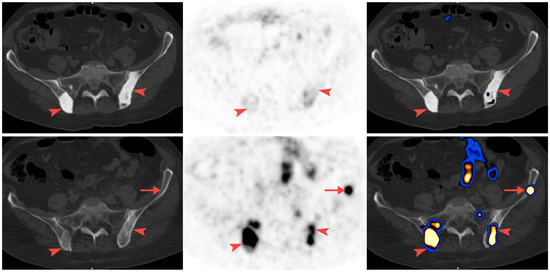

68Ga-PSMA-11 PET/CT Follow-Up of Patients with Prostate Cancer with Bone Metastases Who Had Reduced Bone Density after Androgen Deprivation Therapy

2.2. Positron Emission Tomography/Computed Tomography (PET/CT) Imaging

2.3. Image Analysis